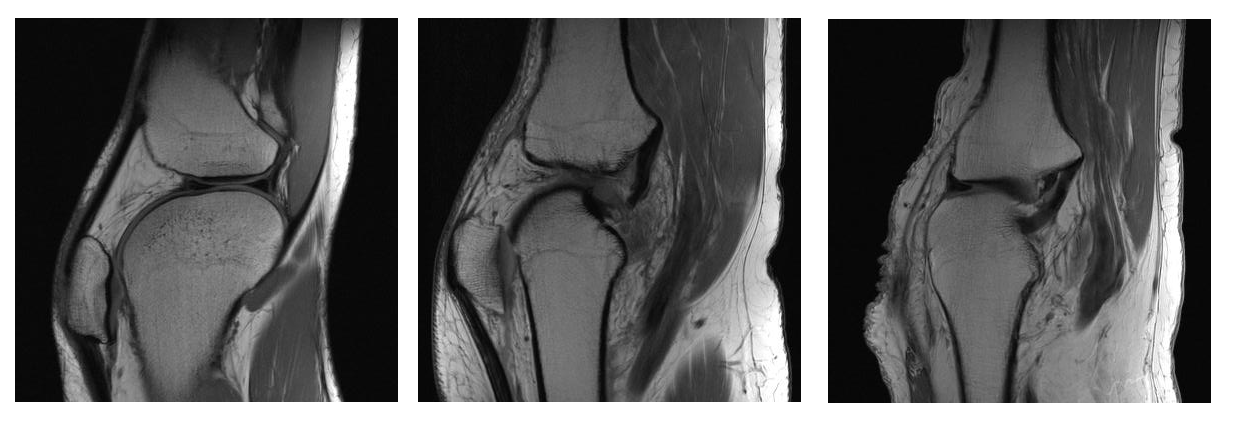

The medical image modality of magnetic resonance imaging (MRI) plays an increasingly important role in modern medicine, despite the high costs of these exams when compared to the decreasing costs of other imaging exams. Despite advances and investments in technologies, the attempt to take advantage of these studies in cost reduction is still modest in recent years.

This research proposal aims to study and evaluate the reconstruction of MRI images with subsampled data in the frequency space (K space) through artificial intelligence (AI), with reduction of the examination time and consequently the exam costs. This study compares the feasibility and efficiency in different percentages of the sample.

The raw data in K space was sampled in a controlled way to reconstruct the images, resulting in an image with sparse data reducing the number of image information. Then, the sparse data undergoes a reconstruction process through AI techniques such as Deep Learning (DL).

The proccess resultss was compared to the original image, analyzing the image efficiency through reconstructed quantitative measures. In this work, the division of the image into separate rows and columns was used and worked as single sequences.

These sequences were used as input to a neural network and reconstructed to form the original sequence, before subsampling. Finally, an algorithm was used to join these sequences and shapes to the new rows and columns of the reconstructed image.

The results of this process were compared with the original image, analyzing the image efficiency obtained through quantitative measures of the quality of the reconstructed images, in this case, the structural similarity index (SSIM) and the mean square error (mean square error) - MSE), for the different subsampling weights in the K space.

Therefore, with this study, it was possible to obtain a more effective method than the conventional method, reducing the time required for this process.